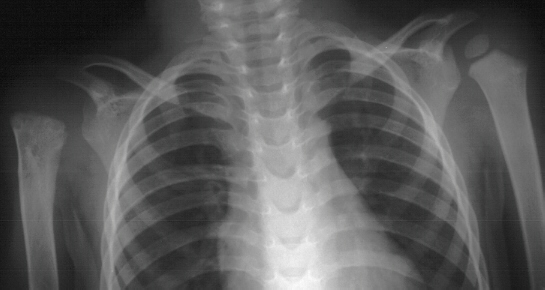

This 3 year boy presented with shortening of the right humerus.

Clinical examination revealed 4 cm shortening of right arm and

painless limitation of ROM of right shoulder; abduction was 150

degrees with 80 degrees at the glenohumeral joint and internal

rotation was significantly limited(image 1). There was also a

1 cm shortening of the right leg and a 10 degree valgus deformity

of the same knee(image 2). Radiological examination showed absence

of proximal epiphysis of the right humerus(image 1)with marked

deformity of the metaphyseal region. By age 11 the child had a